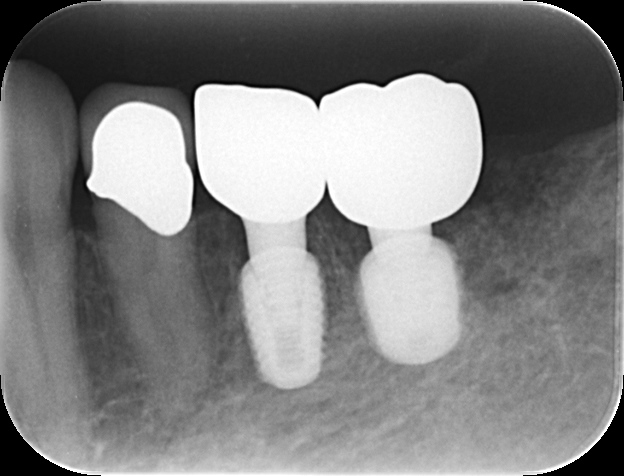

当初は「左下奥歯の違和感」を主訴に来院されました。当院の歯内療法専門医が精密な診断を行ったところ、左下5番(第2小臼歯)に「破折」が認められ、残念ながら抜歯適応との診断となりました。

その後、経過観察中に今度はその奥の左下6番(第1大臼歯)の歯ぐきに「フィステル(おできのような腫れ)」が出現。被せ物を外して内部を確認したところ、過去の根管治療の影響と思われる「穿孔」が確認され、こちらも保存不可という厳しい状況でした。

2. ご来院時の状態と診断

精密検査の結果、以下のことが明らかになりました。

・左下5番: 歯根破折。

・左下6番: 根管内の穿孔。

当院では事前にCTデータを用いたコンピュータシミュレーションを徹底して行います。